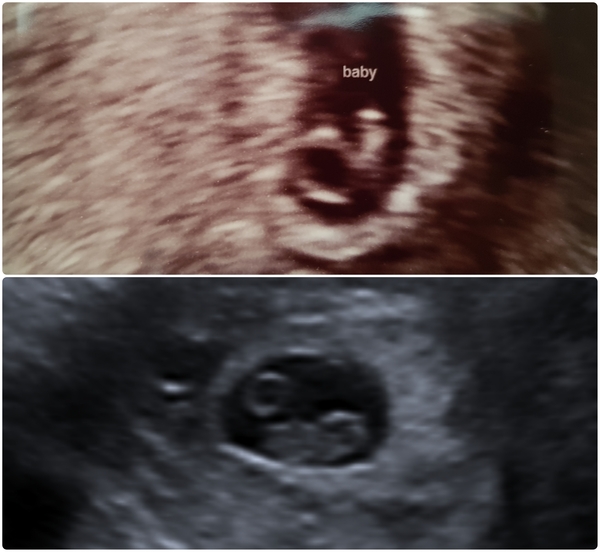

clairehr · 06/07/2018 21:32

Sat here comparing my scans, only a week apart, and dwelling on how amazing this thing we're doing is! There is LIFE inside us ladies 😍

February 2019 part 3